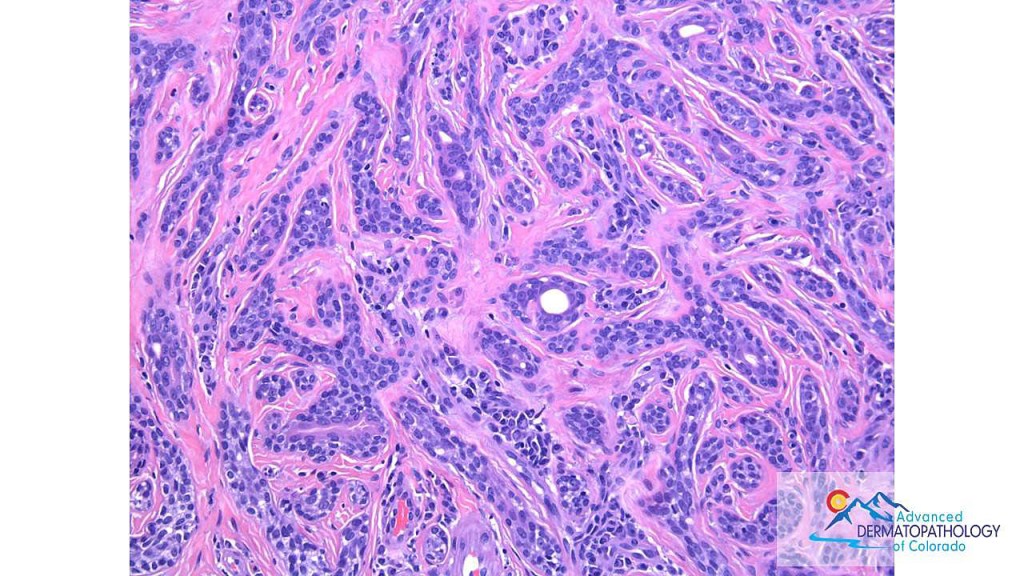

•The epithelium consists of outer myoepithelial cells supporting an inner layer of columnar cells with abundant eosinophilic cytoplasm showing decapitation secretion

•Dense plasma cell infiltrate

•Maligant change- syringocystadenocarcinoma papilliferum is exceptionally rare & is characterised by nuclear pleomorphism, excessive mitotic activity, abnormal mitoses; most cases appear to be clinically low grade